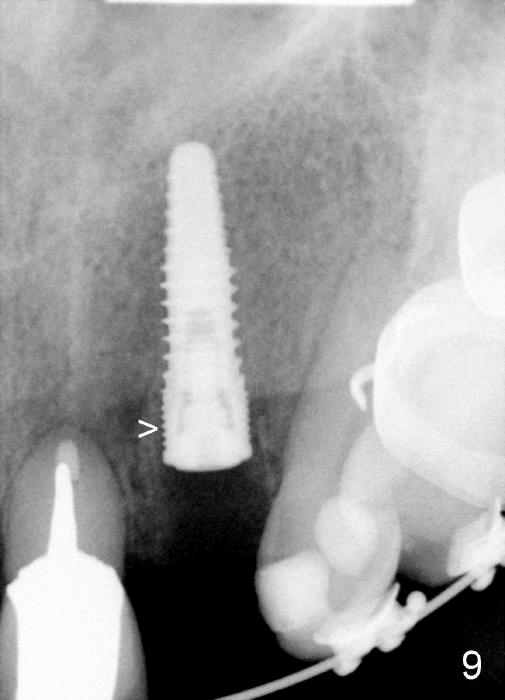

A prominent feature of implant failure in this case is pain. The patient feels that the pain is from the base of the nose. PA taken 3 days postop shows that the implant is inferior to the nasal floor (Fig.2 red ^). Clinically, the buccal gingiva continues to be erythematous 10 days postop (Fig.1). The pain is so unbearable that the implant (3.8x14 mm) is removed 10 days post placement. After repeated debridement, a 4.1 mm tap (Fig.3 T) is manually inserted with torque. A 4.1x14 mm submerged implant is placed with insertion torque < 30 Ncm, but it is placed subcrestally (Fig.4 <--). This time an immediate provisional is not provided. The flap is sutured. The pain disappears immediately. No infection is found 7 days postop (Fig.5). However, an asymptomatic vesicle is noted at the crest 3 weeks postop (Fig.6). The gingiva looks normal 2 and 3 months postop (Fig.7,8). The coronal gap dissolves 3 months postop (Fig.9 >, as compared to Fig.4), suggesting osteointegration. The implant is uncovered 4 months postop (Fig.10). Bracket is placed 5 months postop (Fig.10'). One month later, the left central incisor improves in position coronocervically (Fig.11), but the overjet needs correction by distalization of the upper anterior teeth. The implant at the site of #10 may be used as an anchorage.